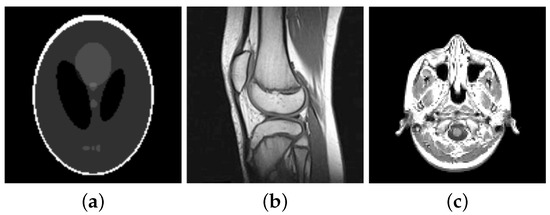

For our numerical studies we consider the images shown in Figure 1 of size 256 × 256 pixels and in Figure 2. The image intensity range of all original images considered in this paper is , i.e., and . Our proposed algorithms automatically transform this images into the dynamic range , here with . That is, let be the original image before any corruption, then . Moreover, the solution generated by the semi-smooth Newton method is afterwards back-transformed, i.e., the generated solution is transformed to . Note that is not necessarily in , except .

Figure 2.

Original images (a) Shepp-Logan phantom of size pixels (b) knee of size pixels (c) slice of a human brain of size pixels.

6.3.6. Reconstruction from Sampled Radon-Data

In computerized tomography instead of a Fourier-transform a Radon-transform is used in order to obtain a visual image from the measured physical data. Also here the data is obtained along radial lines. Here we consider the Shepp-Logan phantom, see Figure 14a, and a slice of a body, see Figure 15a. The sinogram in Figure 14a and Figure 15b are obtained by sampling along 30 and 60 radial lines, respectively, Note, that the sinogram is in general noisy. Here the data is corrupted by Gaussian white noise with standard deviation , whereby for the data of the Shepp-Logan phantom and for the data of the slice of the head. Using the inverse Radon-transform we obtain Figure 16a,b, which is obviously a suboptimal reconstruction. A more sophisticated approach utilizes the -TV model which yields the reconstruction depicted in Figure 16b,e, where we use the pAPS-algorithm and the proposed primal-dual algorithm with . However, since an image can be assumed to have non-negative values, we may incorporate a non-negativity constraint via the box-constrained -TV model yielding the result in Figure 16c,f, which is a much better reconstruction. Also here the parameter is automatically computed by the pAPS-algorithm and the non-negativity constraint is incorporated by setting in the semi-smooth Newton method. In order to compute the Radon-matrix in our experiments we used the FlexBox [52].

Figure 16.

Reconstruction from noisy data. (a) Inverse Radon-transform (PSNR: 29.08; MSSIM: 0.3906); (b) -TV (PSNR: 29.14; MSSIM: 0.4051); (c) Box-constrained -TV (PSNR: 33.31; MSSIM: 0.6128); (d) Inverse Radon-transform (PSNR: 31.75; MSSIM: 0.3699); (e) -TV (PSNR: 32.16; MSSIM: 0.3682); (f) Box-constrained -TV (PSNR: 36.08; MSSIM: 0.5856).